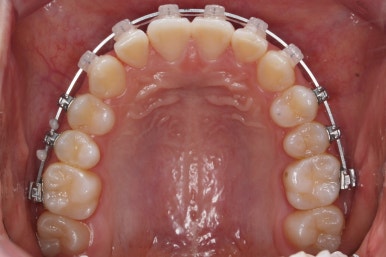

치료 종료 후의 모습입니다.

치아들이 가지런하게 되었고, 나오지 못하던 치아도 잘 나와서 가지런해졌습니다.

해당 부위 앞뒤로 쓰러져 있던 치아들도 축이 바로 잡혔고, 자연스레 위-아래 치아의 중앙선도 맞아졌습니다.

치아가 잘 올라온 것을 볼 수 있습니다.

이제 전후 비교입니다.

16개월만에 굉장히 좋아진 모습입니다.